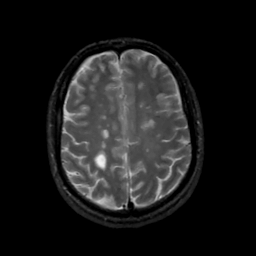

MR Study #12, May 12, 1991 -- Slice #36